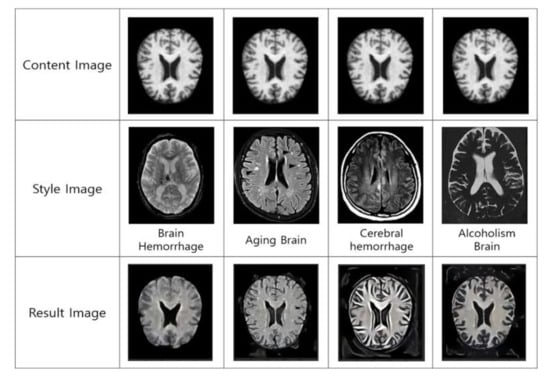

Style transfer uses the features of the VGG19 network consisting of convolution, pooling layers, and an FC layer. The model in Figure 5 is divided into the extractor and the classifier of features. The input image is divided into a content image and a style image. From each convolution layer and each pooling layer, the features of the content image and style image are extracted, respectively. In addition, the FC layer and SoftMax layer features are calculated, classified, and predicted to transfer the style. Figure 6 shows the result of the image style transfer. The content image is the normal human brain image. The style image is the recollected brain image. The resulting image is the result extracted by transferring the attributes of the style image to the content image.

Figure 6.

Result of image style transfer.

As a result of the transfer of image style in Figure 6, the style of dementia factors in normal brain conditions is applied; therefore, there are changes in brain volume. Thus, dementia factors have serious impacts on dementia as well as cognitive disorder; it is necessary to be careful when managing and preventing it.